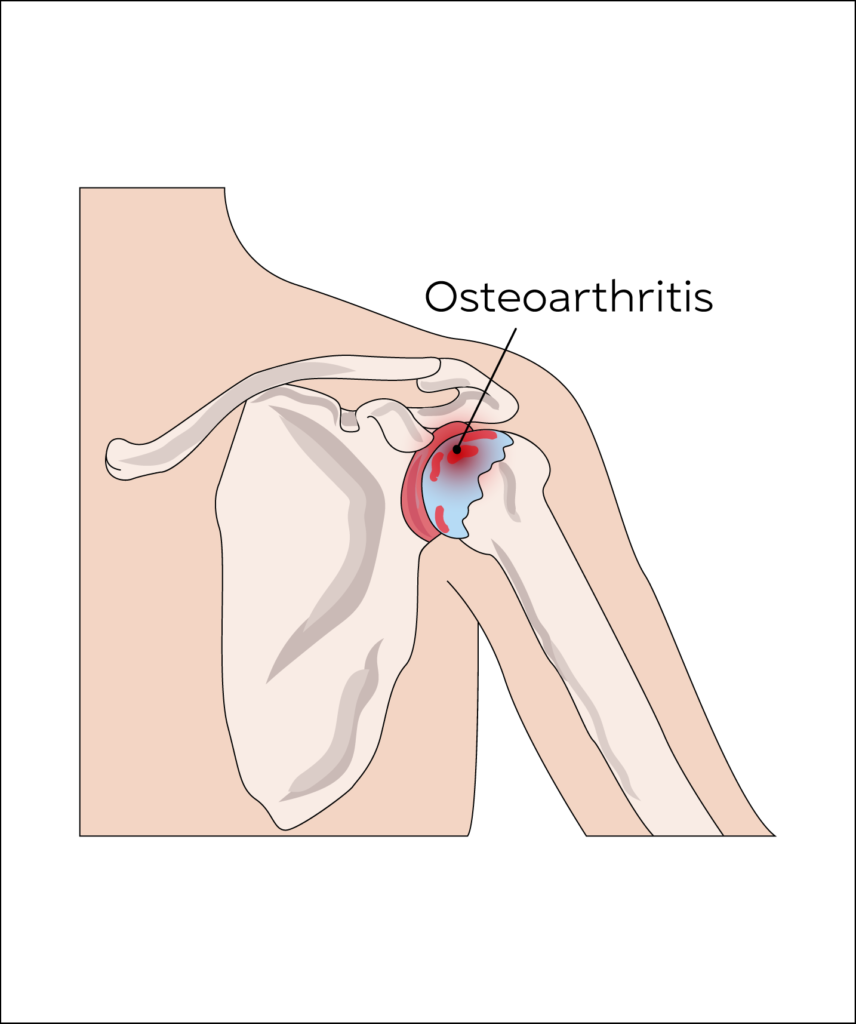

Osteoarthritis

Osteoarthritis is a painful condition affecting any joint with articular cartilage due to gradual wear and tear of the articular cartilage, which protects the bone ends.

It is more common in those aged over 50 and especially more in females and a family history.

Dull deep seated shoulder pain with grinding and clicking sensation on shoulder movements. Restriction and pain early in the morning worsen, as the condition progresses alongside limitation of overhead activities.

Ultrasound Guided Injection therapy when combined with physical therapy offers good symptomatic relief in painful osteoarthritis. Targeted injection under ultrasound guidance using steroids or Hyaluronic acid are effective in pain relief.